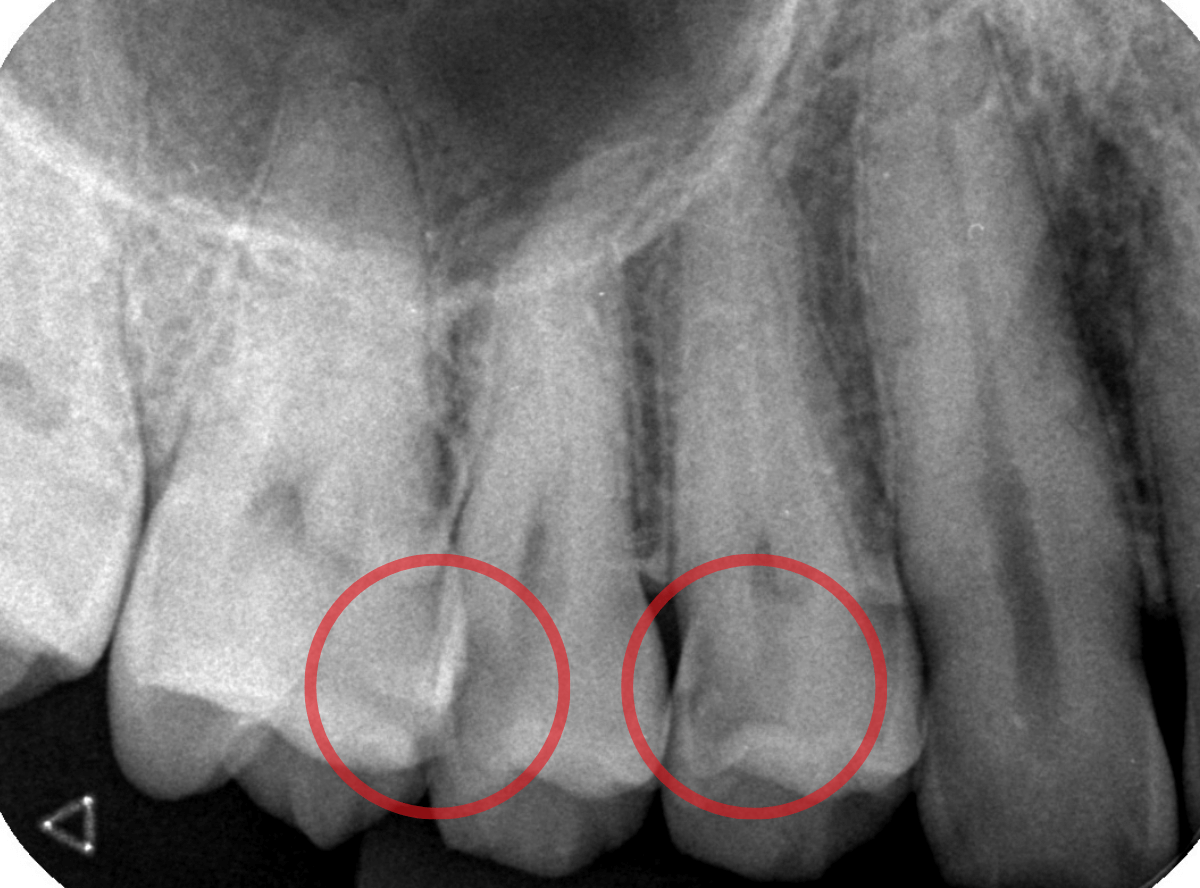

Case.22 痛みはないけど、歯のすきまから大きな虫歯

上の小臼歯の間が虫歯になっていた患者さんです。

症状はありませんし、見た目からも虫歯があるかはわかりませんでした。

レントゲン写真で確認します。

赤い線が虫歯、青い線が歯の神経です。

歯のすきまから両側に虫歯が大きく広がっているのが確認できます。